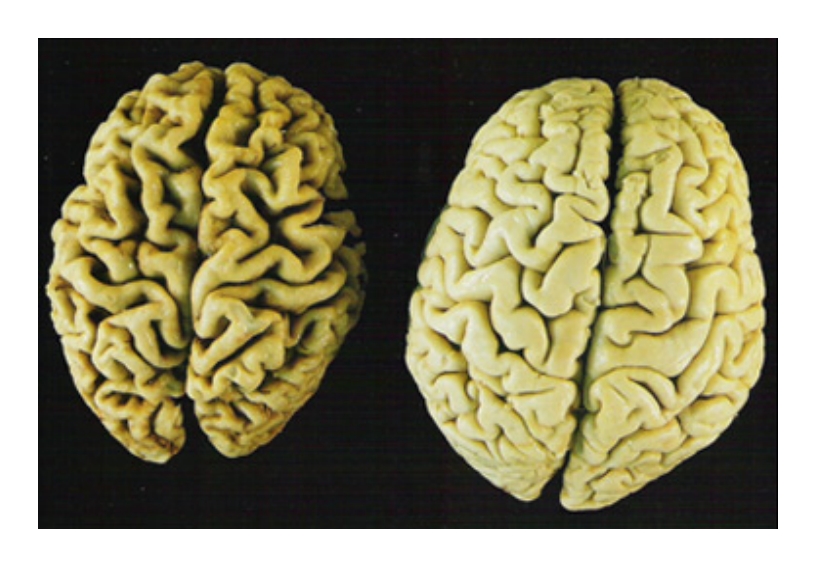

massa cerebrale ridotta a sx, normale a dx

Molte proteine, invece, possono letteralmente ridurre la massa cerebrale, e portare allo sviluppo dell’Alzheimer”, ha detto Sam Gandy, ricercatore a capo dello studio. Gandy e colleghi hanno studiato gli effetti della dieta su dei topi di laboratorio, allevati specificatamente per sviluppare l’Alzheimer. “Abbiamo verificato gli effetti di una dieta regolare, una a bassi carboidrati e molti grassi, una ad alti carboidrati e pochi grassi, e una con molte proteine e pochi carboidrati”, ha detto Gandy. “Dopodiche’ abbiamo esaminato i cervelli dei topi – ha continuato – misurando i livelli di proteine responsabili della formazione di placche amiloidi dell’Alzheimer”. La dieta di tipo mediterraneo, con pochi grassi e molte verdure, frutta e pesce, e’ risultata la migliore, in quanto capace di rallentare il progresso dell’Alzheimer o ritardare la sua insorgenza, un risultato confermato anche da studi precedenti. “La dieta con molti grassi ha invece alzato i livelli di proteine amiloidi, ma senza avere effetto sui topi”, ha detto Gandy. “Il risultato veramente sorprendente, tuttavia, e’ stato quello ottenuto dalla dieta ad alti carboidrati. C’e’ stata una perdita di massa cerebrale, che ha reso i cervelli piu’ piccoli e piu’ suscettibili alla formazione di placche”, ha aggiunto. Sulle proteine, spiega Gandy, sono spesso basate delle diete per perdere peso, diete che spesso riducono anche l’ammontare di carboidrati. “Queste diete sono doppiamente dannose: i grassi aumentano l’accumulo delle placche, e le molte proteine sensibilizzano le cellule del cervello alle sostanze tossiche rilasciate dalle placche. Una dieta di questo tipo potrebbe effettivamente predisporre all’insorgenza dell’Alzheimer e a riduzione della massa del cervello”, ha concluso Gandy.